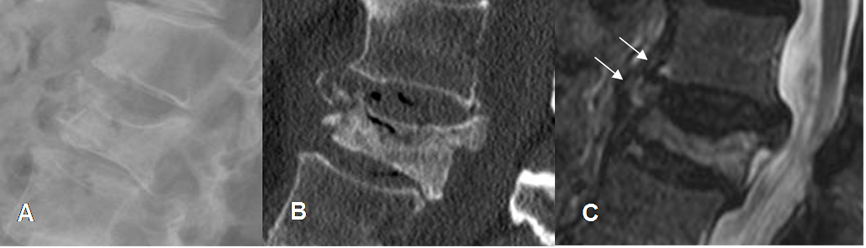

Fig 186. Fractura inestable.

A: Rx lateral, B: TAC reconstrucción sagital y C: RM sagital en T2. Fractura inestable, con fragmento retropulsado. El ligamento común anterior está separado del cuerpo vertebral, pero permanece íntegro.